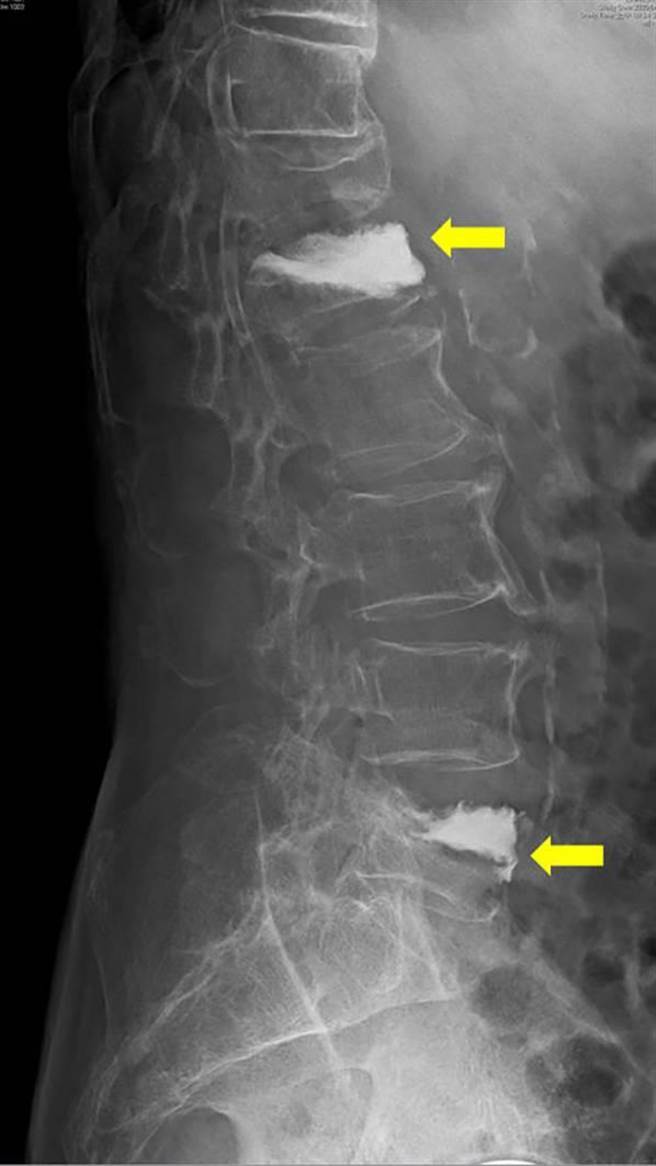

脊椎骨折別輕忽 你以為的脊椎壓迫性骨折有可能是 爆裂性骨折

脊椎骨折分類 Dr Shui

好痛喔 老婦2處脊椎壓迫性骨折拔個菜突跌坐在地 寶島 中時